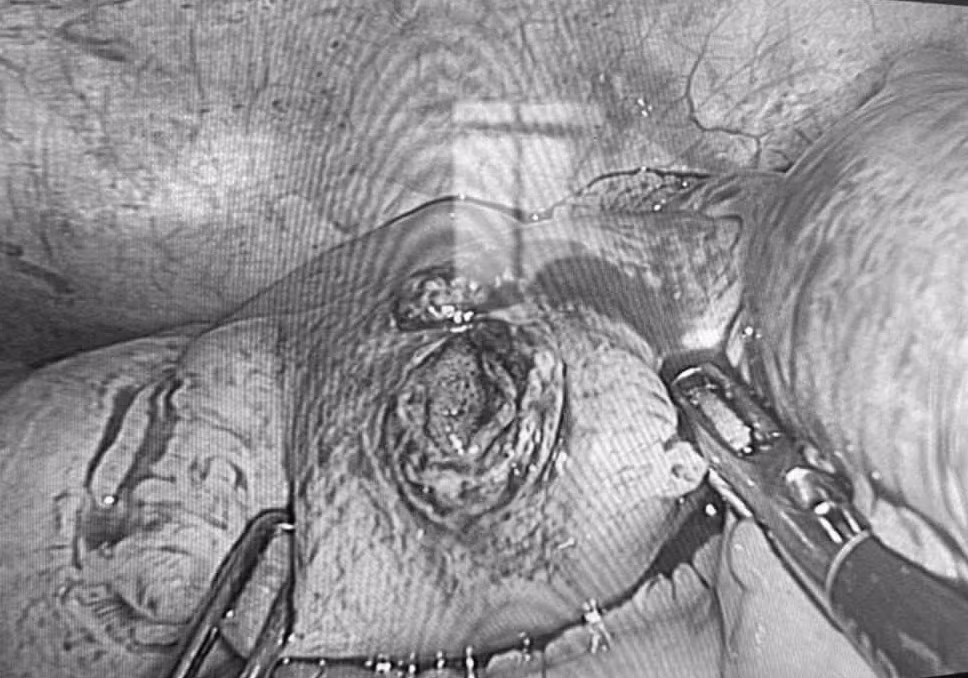

Chiếc đinh được các bác sĩ phẫu thuật nội soi lấy ra - Ảnh BVCC

Bác sĩ Phan Lê Khanh, người trực tiếp phẫu thuật, cho biết đây là trường hợp may mắn vì bệnh nhân được đưa đến bệnh viện sớm. Nhờ đó, ổ bụng còn khá sạch, không ghi nhận thức ăn hay dịch tiêu hóa tràn ra ngoài.

Trong quá trình thám sát, ê-kíp không phát hiện tổn thương đại tràng hay các mạch máu lớn, giúp ca phẫu thuật diễn ra thuận lợi.